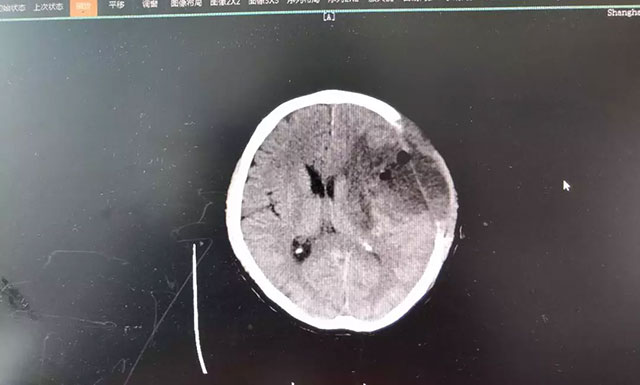

“是不是中風(fēng)了?”家人看情況不妙,趕緊將錢先生送到當(dāng)?shù)蒯t(yī)院檢查。CT影像報(bào)告顯示,患者大腦左顳葉占位。隨后幾天,錢先生的癥狀出現(xiàn)反復(fù)和惡化,考慮到當(dāng)?shù)蒯t(yī)療資源條件較為有限,家人將其轉(zhuǎn)至上海藍(lán)十字腦科醫(yī)院,作進(jìn)一步診斷治療。